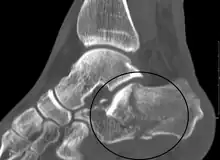

The Angle of Gissane, or "Critical Angle", is the angle formed by the downward and upward slopes of the calcaneal superior surface. On a lateral radiograph, an angle of Gissane > 130° suggests fracture of the posterior subtalar joint surface. Bohler's angle, or the "Tuber Angle", is another normal anatomic landmark seen in lateral radiographs. It is formed by the intersection of 1) a line from the highest point of the posterior articular facet to the highest point of the posterior tuberosity, and 2) a line from the former to the highest point on the anterior articular facet. Bohler's angle is normally 25° to 40°.[13] A decreased angle is indicative of a calcaneal fracture.